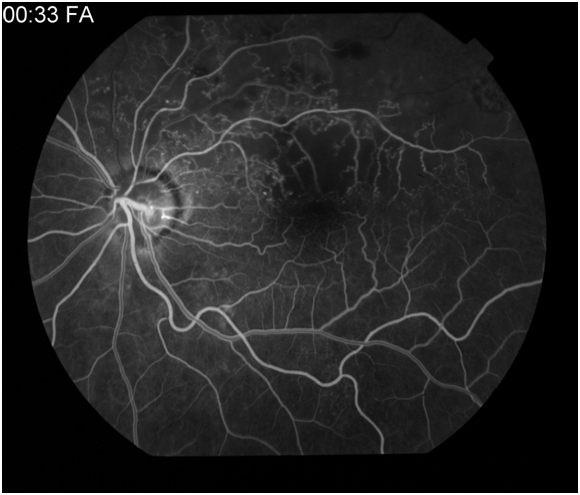

Figure 2: Red-free photo, early arteriovenous phase, peak phase , and late phase angiogram of a left eye with choroiditis. Early angiogram demonstrates hypofluorescence of the choroidal lesions with the development of circumferential hyperfluorescence and leakage in the later stages of the angiogram.